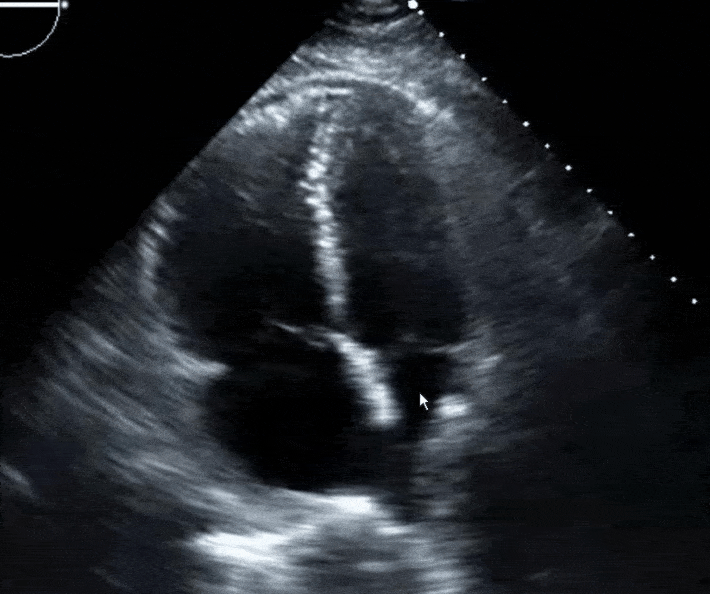

Right ventricular dysfunction can be assessed objectively by electrocardiography, echocardiography, computed tomogrpahy or by elevated brain natriuretic peptide. Examples of electrocardiographic signs of right ventricular strain include new right bundle branch block and antero-septal ST segment changes. The most specific sign of pulmonary embolism related right ventricular dysfunction on echocardiography is McConnell sign. McConnell sign is normal apical movement with mid-wall akinesia.

Other echocardiographic signs of right ventricular strain include right ventricular dilatation, new onset tricuspid regurgitation, septral flattening, lack of respiratory variation of the IVC and right ventricular hypokinesia. Computed tomogrpahic signs of right ventricular dysfunction include ventricular dilatation, contrast filling the IVC, dilatation of the main pulmonary artery and septal flattening. Myocardial necrosis is diagnosed by elevated troponin.